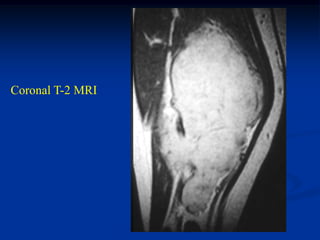

Case #252

11 year male

desmoid posterior

compartment thigh

Coronal T-1 MRI

Coronal T-2 MRI

Axial T-2 MRI